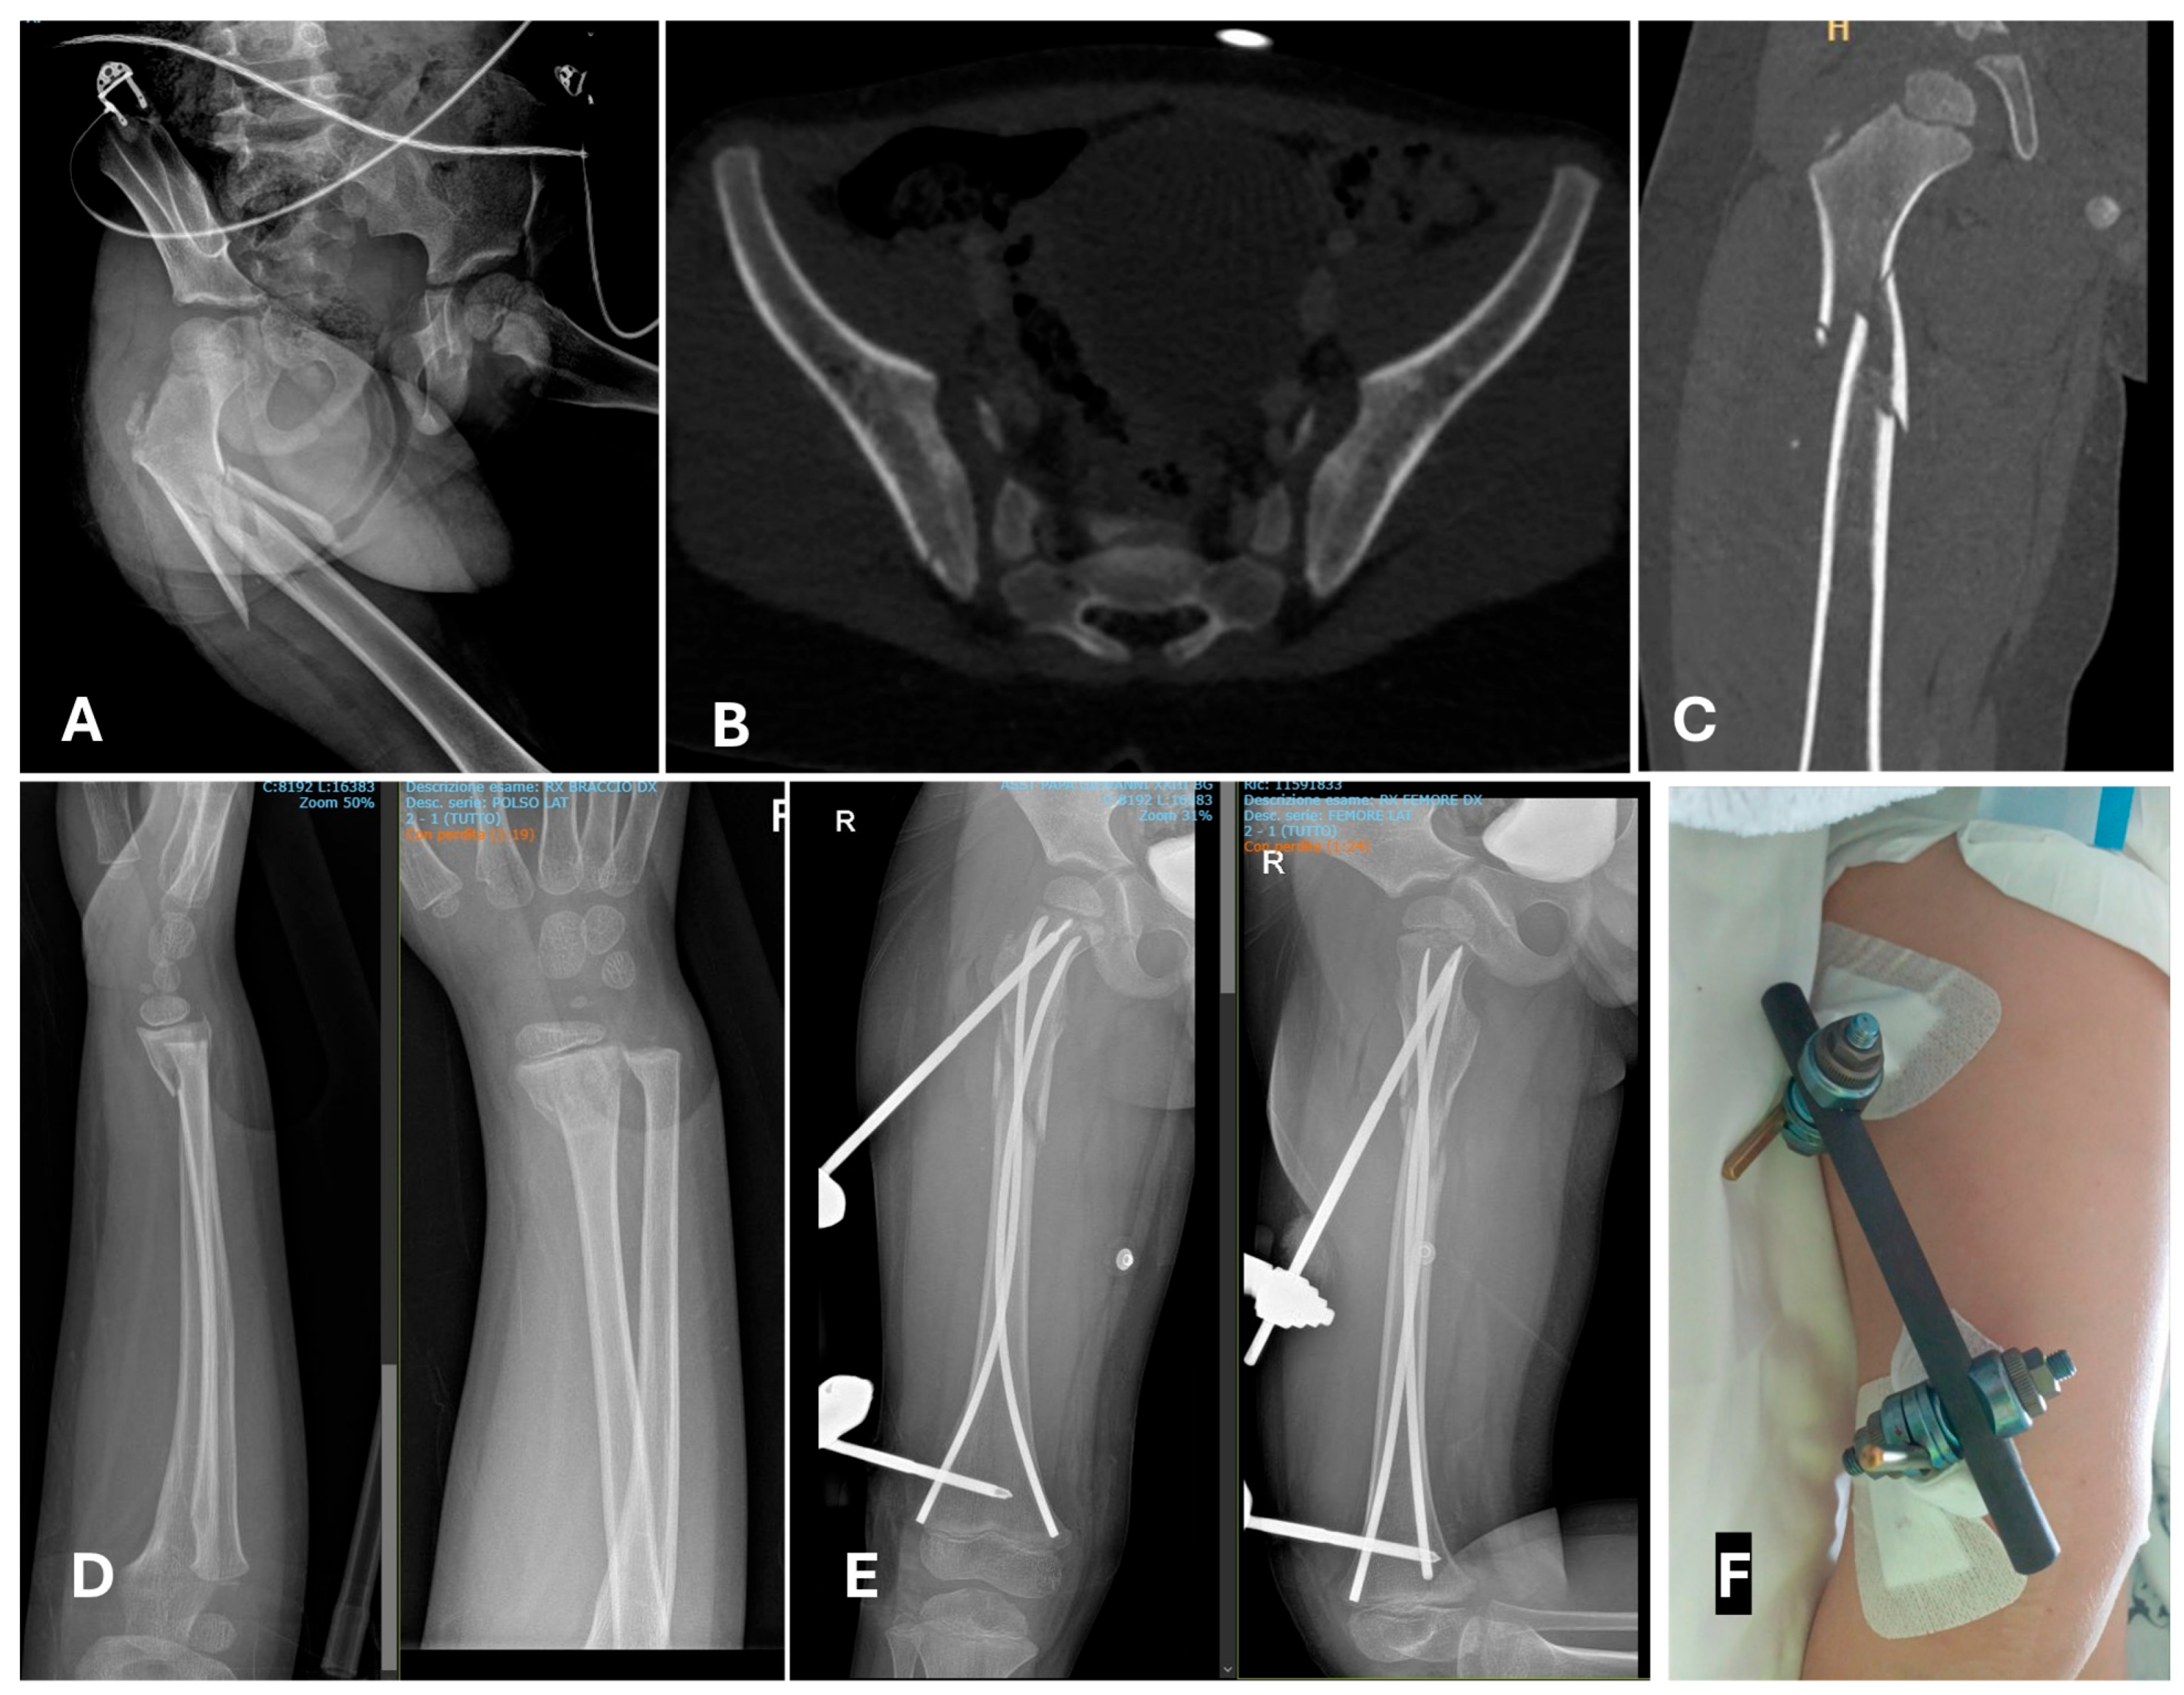

- In the age-group 15–17 years, 23/23 (100%) cases were treated with temporary external fixation (ExFix);

- In the age group 12–14 years, 9/14 (64%) cases were treated with ExFix, and 5/14 (26%) cases were treated with elastic stable intramedullary nails (ESIN);

- In the age group 5–11 years, 1/5 (20%) cases were treated with ExFix, and 4 cases were treated with ESIN;

- In the age group 0–4 years, 2/4 (50%) cases were treated with ESIN, and 2/4 (50%) cases were treated with a hip spica cast.